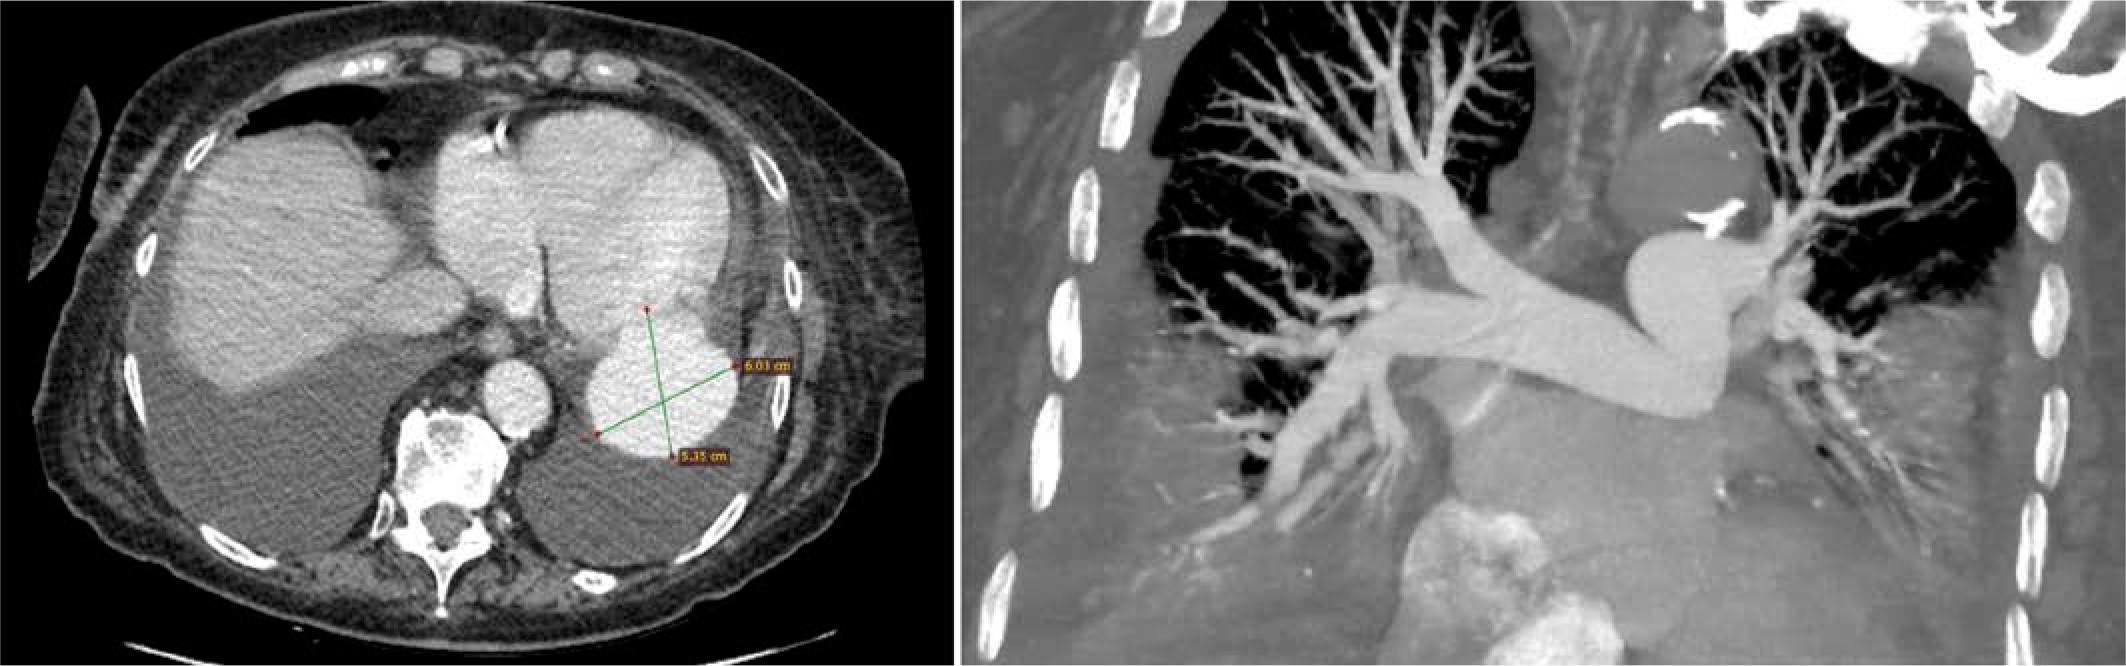

FIGURE 2.